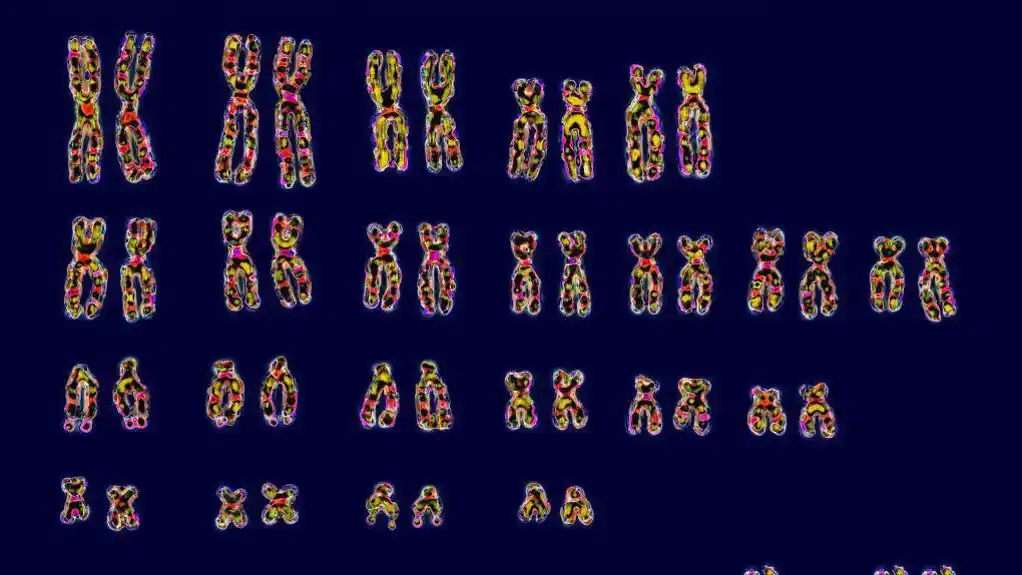

Tokom medicinskog pregleda, ginekolog je naložio da se uradi analiza kariotipa koja omogućava detaljno ispitivanje hromozoma pojedinca, obično iz uzorka krvi.

Rezultati su pokazali prisustvo XY hromozoma u njenoj krvi, što je zbunilo i Anu i lekare.

Upoređivanje njihovog DNK pokazalo je da su krvne ćelije Ane Paule, ali samo krvne ćelije, identične koje ima njen brat blizanac.

Imala je iste karakteristične genetičke markere.

„U DNK njenih usta, u DNK njene kože – ona je svoja, jedinstvena“, kaže profesor Masijel.

Slučaj Ane Paule predstavlja primer himerizma, kada organizam ima različite genetske setove u različitim tkivima ili organima.

Ona je zatim počela da proizvodi krv sa XY hromozomima, dok su XX ostali u drugim delovima njenog tela.

Genetička analiza pokazala je da dete ima DNK kakav se očekuje – polovina hromozoma potiče od majke, a polovina od oca, i nema ništa od ujaka.